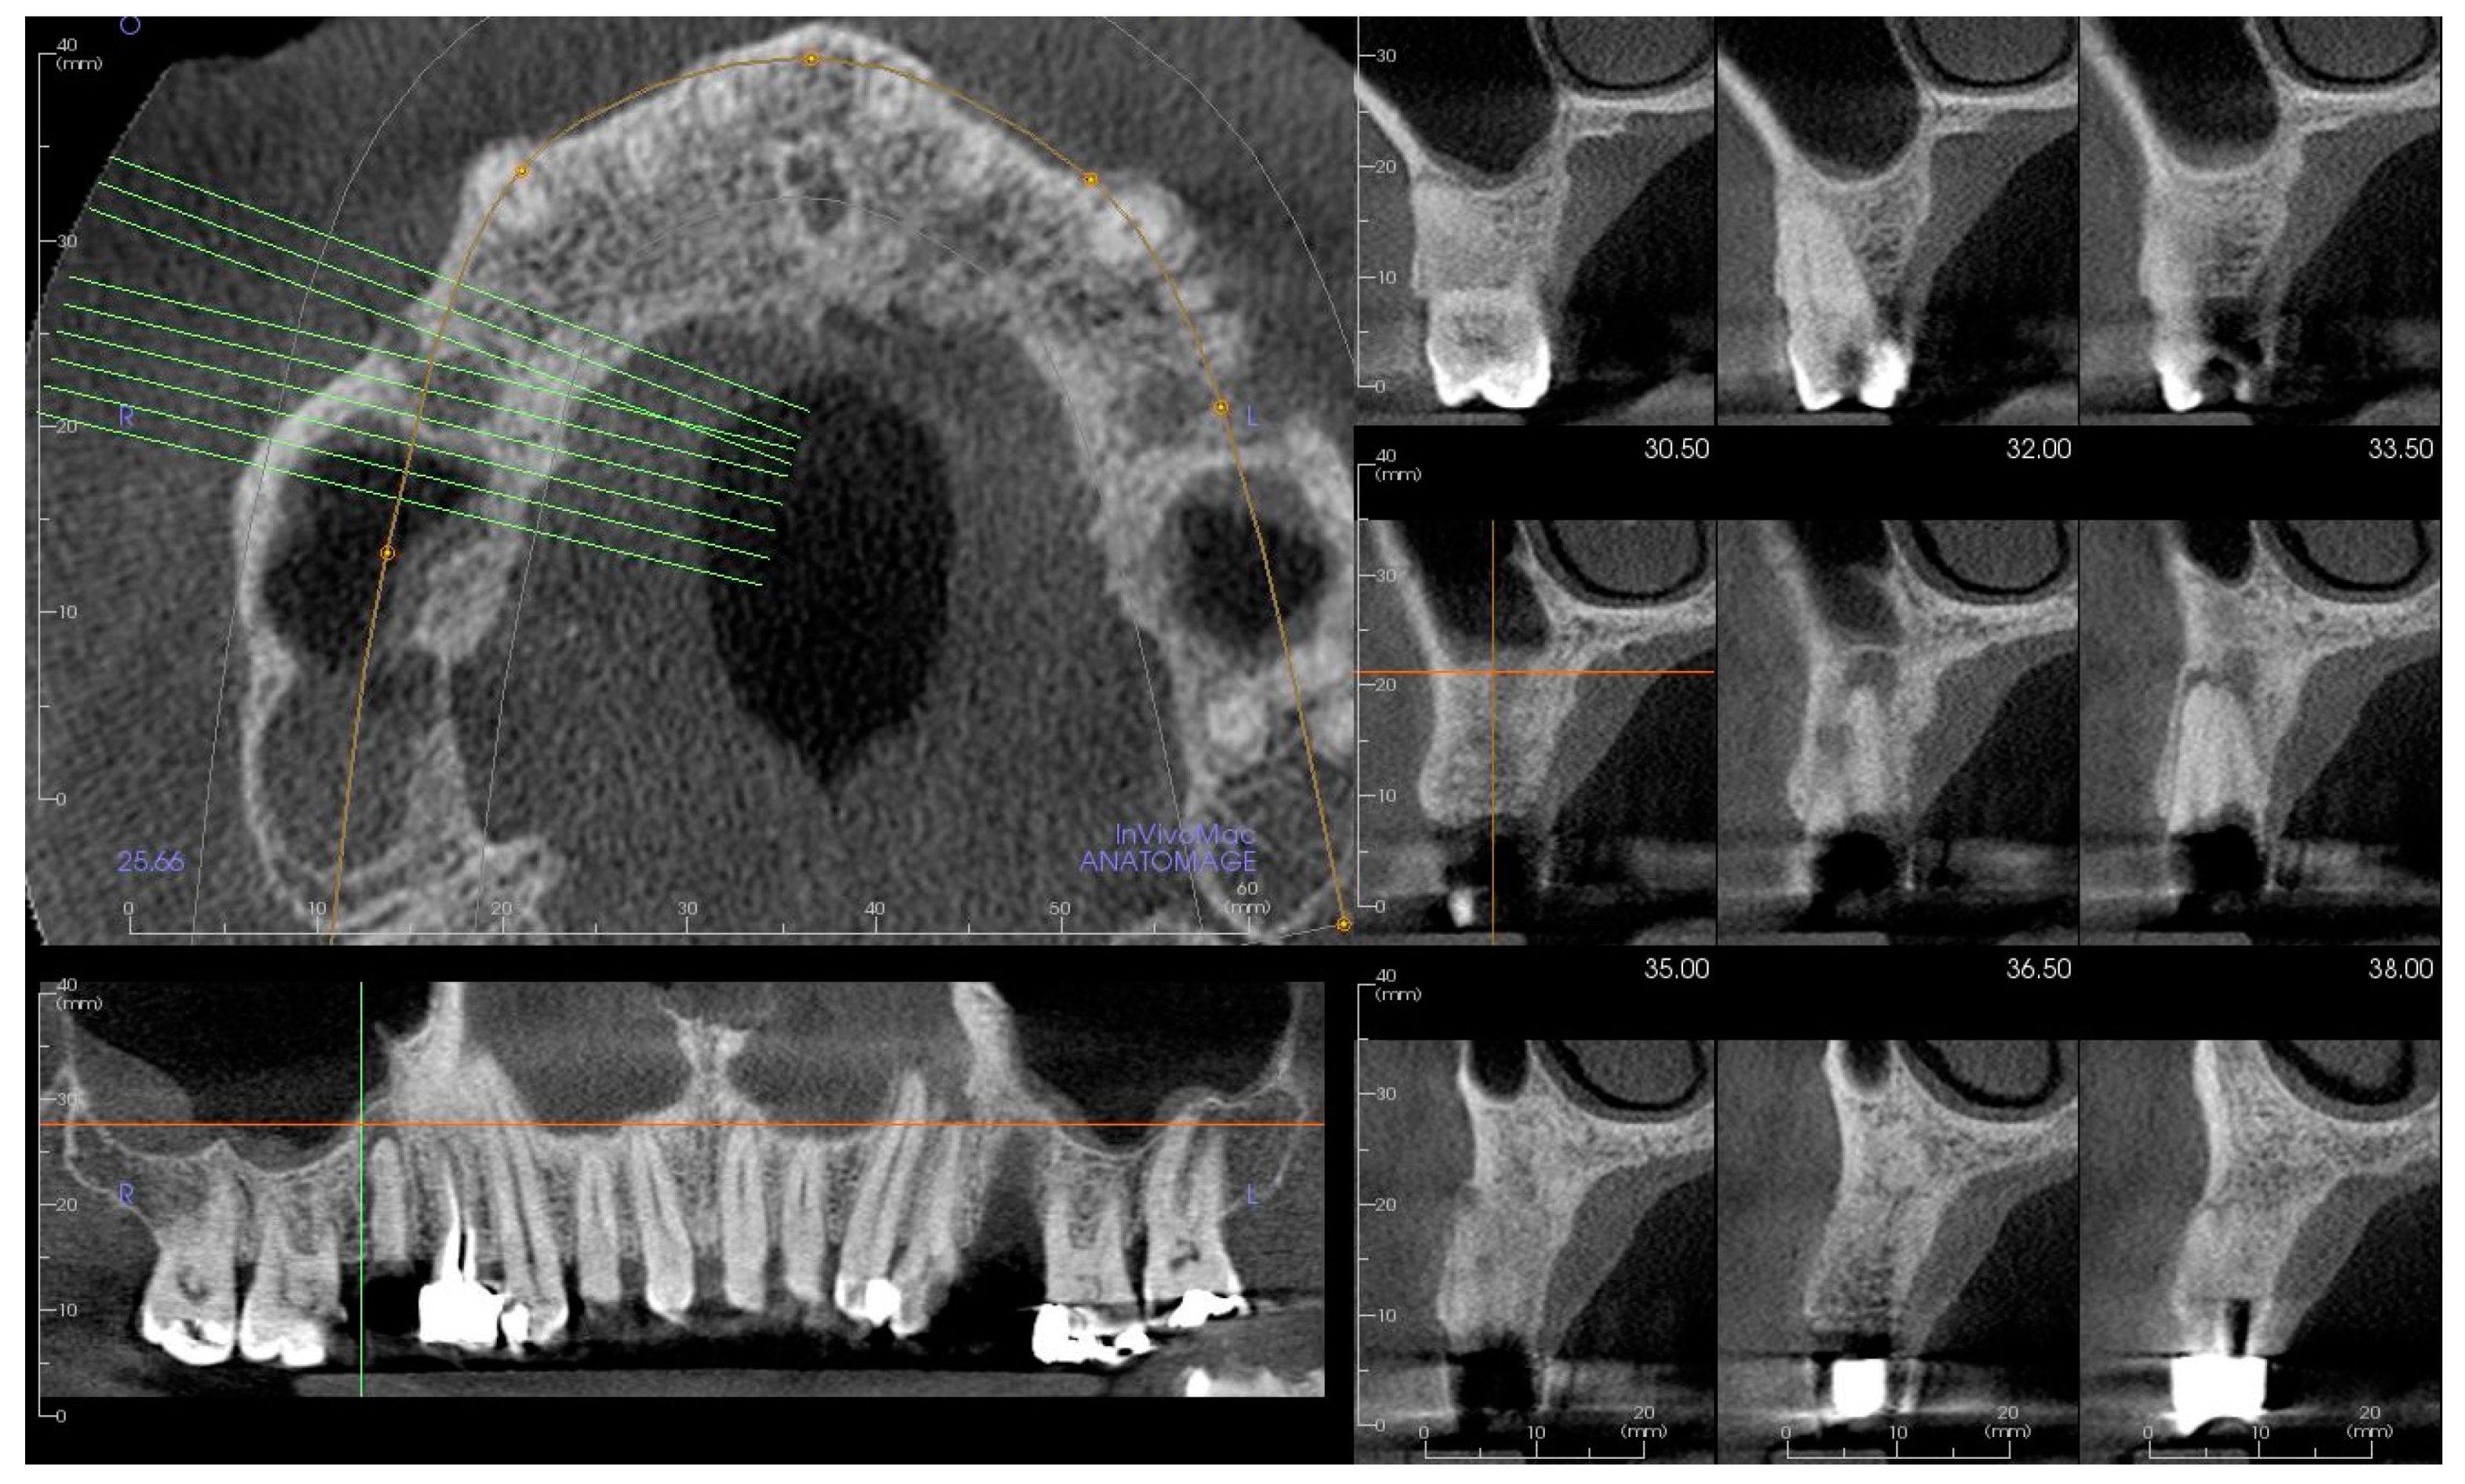

2. Materials and Methods